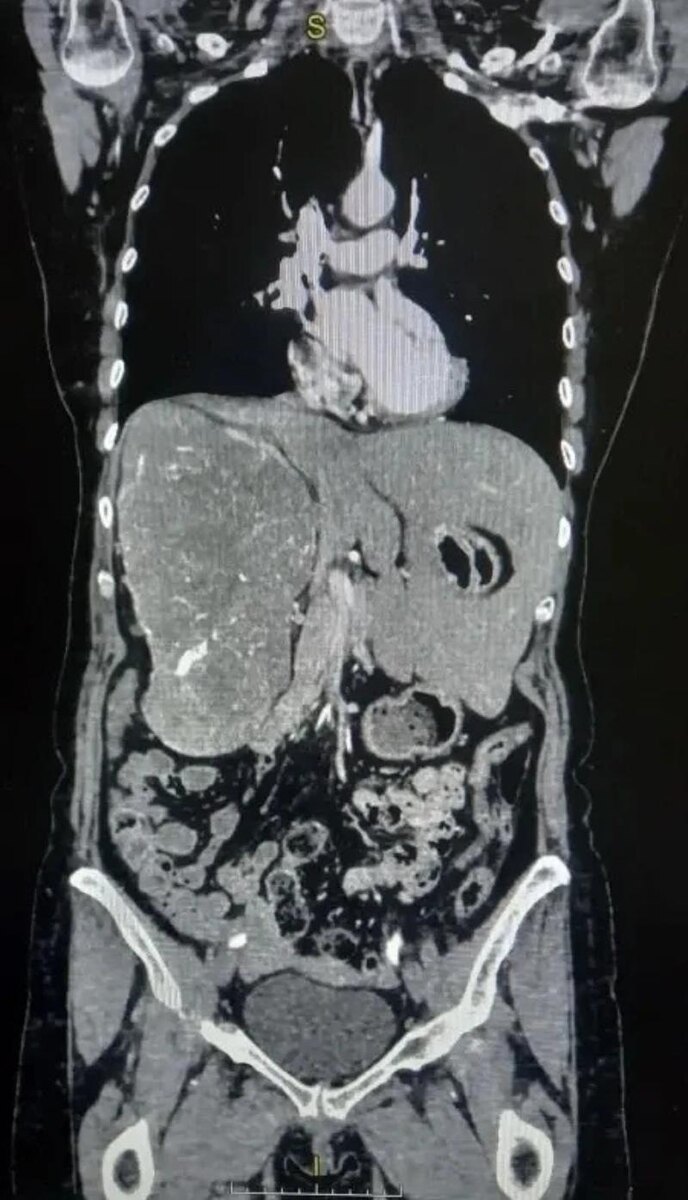

Врачи Волгоградского областного онкологического диспансера провели сложную операцию пациентке с гигантской опухолью почки. Новообразование достигло таких размеров, что сместило внутренние органы: печень оказалась вытеснена из правой части брюшной полости в левую.

Женщина долгое время жаловалась на тупую боль в пояснице и чувство тяжести в животе. После обследования с помощью компьютерной томографии врачи обнаружили крупную опухоль, которая практически полностью заняла правую сторону брюшной полости. Исследования показали, что функция правой почки была почти полностью утрачена. Размер новообразования составил более 20 сантиметров. Медики приняли решение о проведении операции. Из-за больших размеров опухоли выполнить вмешательство малоинвазивным способом было невозможно, поэтому хирурги провели открытую операцию — радикальное удаление правой почки.

Операцию выполнила команда специалистов онкоурологического отделения. Несмотря на сложность случая, хирургам удалось полностью удалить опухоль. По результатам гистологического исследования был подтверждён диагноз — светлоклеточная карцинома. При этом новообразование не успело прорасти в соседние органы, а лишь сильно сместило их, сообщили в пресс-службе облздрава Волгоградской области.